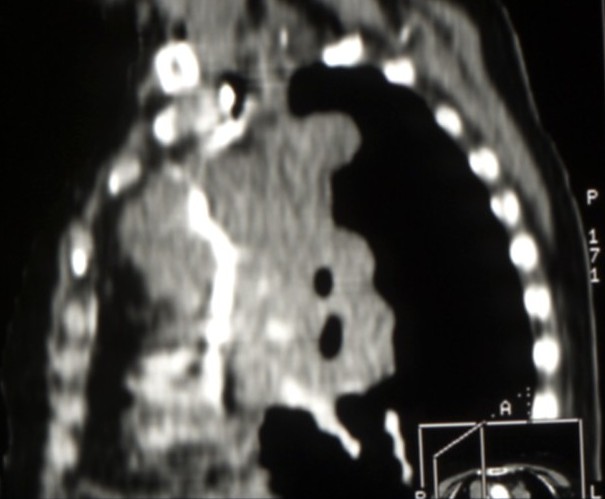

Cancers bronchiques